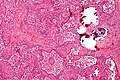

Gondaloblastoma. H&E stain. | |

| LM | immature germ cells (resembling Sertoli cells or granulosa cells),[citation needed] primitive germ cells resemble those of a dysgerminoma, +/-calcification (very common), +/-eosinophilic basement membrane material between the (primitive) germ cells and support cells. |

Gonadoblastoma is a rare germ cell tumour with sex cord elements.

- A mixed tumour that consists of (1) primitive germ cells and (2) sex cord elements.

Features:[1]

- Immature germ cells resembling Sertoli cells or granulosa cells.[citation needed]

- Sertoli cells = moderate cytoplasm in a trabecular or tubular architecture.

- Granulosa cells = form follicle-like structures.

- May form nests.

- Primitive germ cells resemble those of a dysgerminoma.

- Polygonal cells with a central nucleus, squared-off nuclear membrane and clear cytoplasm.

- +/-Calcification (very common).

- +/-Eosinophilic basement membrane material between the (primitive) germ cells and support cells.[2]